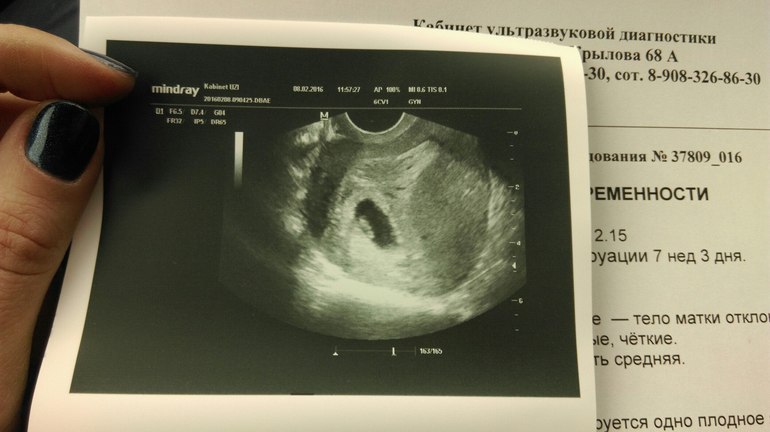

У меня в 7+3 по мес ктр эмбриона уже был 16,5, поставили 8 нед. Хоть буду знать, как выглядит малыш на таком сроке, мне не показали, к сожалению((